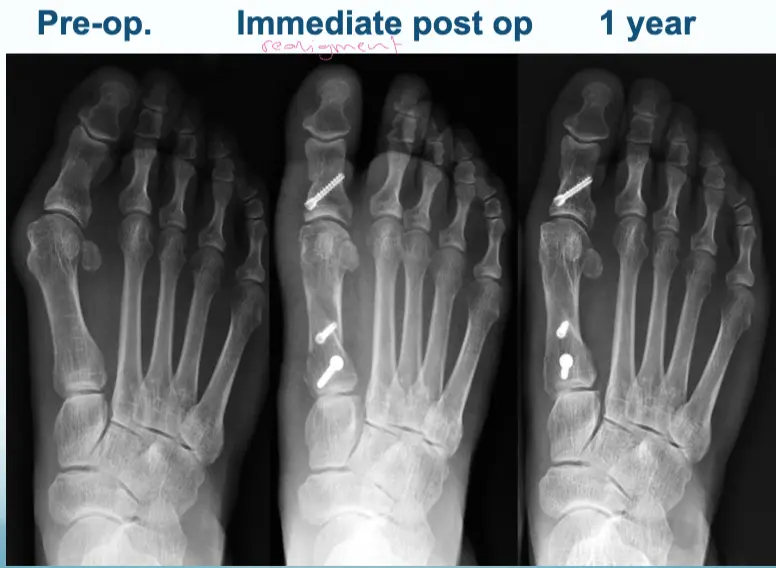

Treatment - Hallux Valgus

Adult:

- Surgery usually

- Many operations

Aim:

- Re-align the 1st metatarsal

- Correct valgus deformity of big toe

- Soft tissue balancing